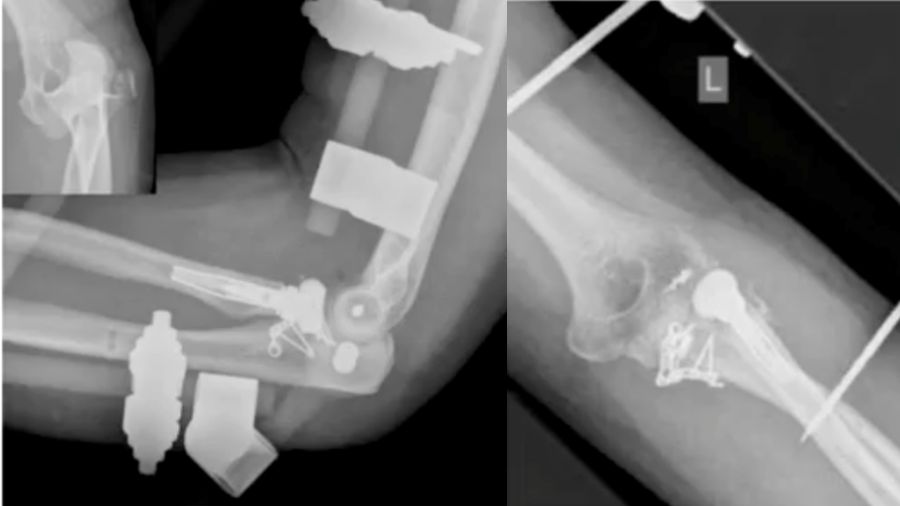

An 88-year-old patient with a terrible triad had an external fixator placed. A cemented prosthesis was chosen due to her age but encountered complications with cement leakage. Thankfully, no neurovascular damage occurred.

Case 4: 94-year-old woman

In this case, a total elbow prosthesis was chosen for a 94-year-old patient with severe trauma. The prosthesis was repositioned but eventually dislocated again, highlighting the complexities of managing such advanced injuries in older patients.

Case 5: 46-year-old male, athlete

A 46-year-old athlete with a comminuted coronoid fracture and severely damaged radial head required multiple surgeries after an overstuffed radial head prosthesis caused complications. The final solution was a total elbow prosthesis, underscoring the importance of careful prosthesis sizing and ligament repair.